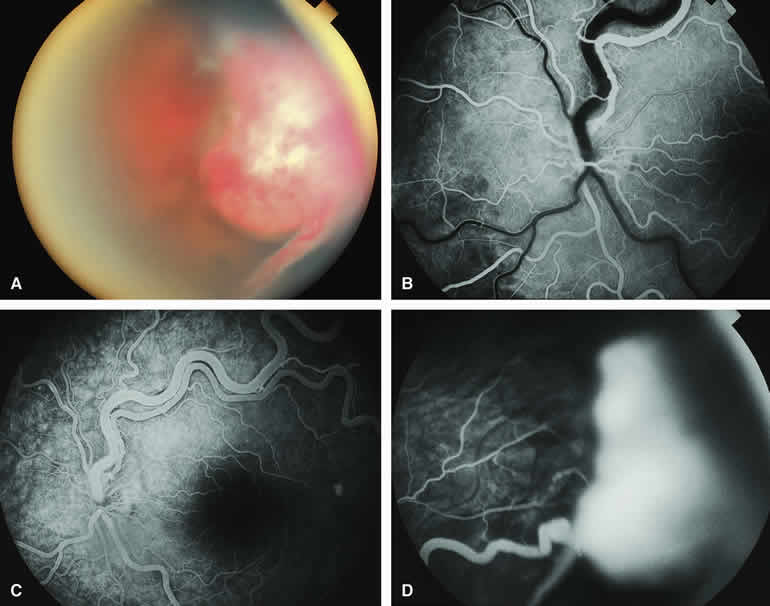

A blister of serous subretinal fluid sometimes develops over and around a presumed choroidal nevus (Fig. 7A), especially if the lesion is located in the macula.11 If one performs a fluorescein angiogram on a small melanocytic choroidal lesion (nevus versus melanoma) that has shallow overlying serous subretinal fluid (see Fig. 7B, C, and D), one or more hyperfluorescent leak sites may show up slowly at the RPE level as the study progresses. In some cases, fluorescein will clearly leak from those foci into the overlying serous subretinal fluid. ICG angiography does not show hyperfluorescent leak sites at the RPE level as well as fluorescein angiography does.

Choroidal Nevus Versus Melanoma with Overlying Serous Subretinal Fluid